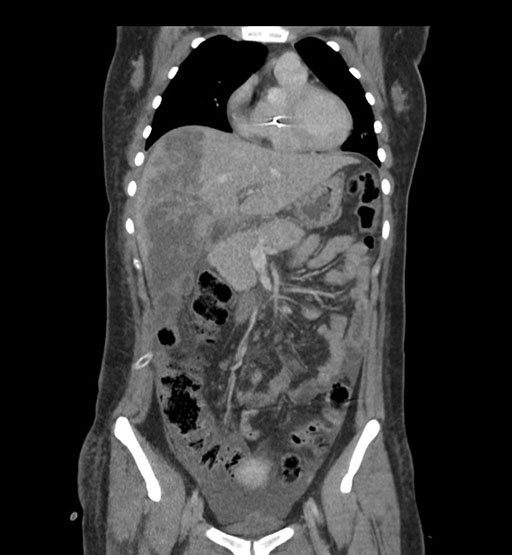

Coronal Arterial